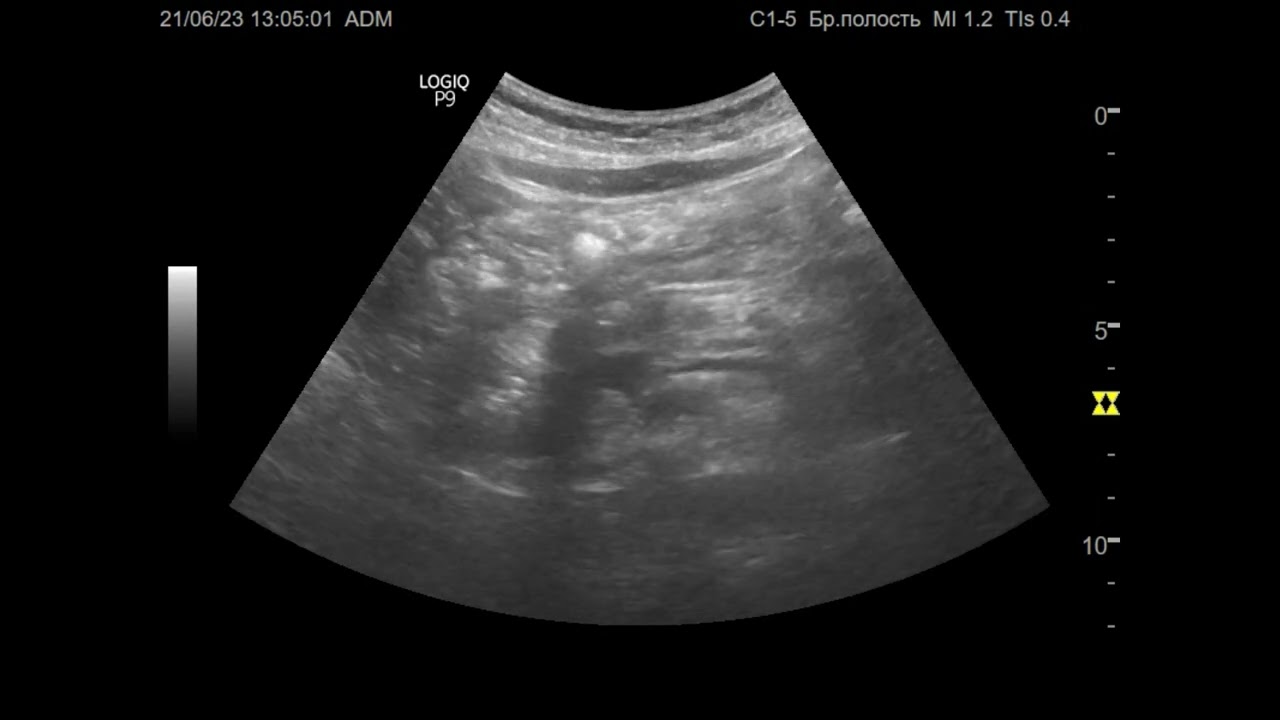

Ультразвуковая диагностика (УЗИ). Доктор Иогансен. Видеопримеры. Выпуск 21. Асцит.

Представлены видеопримеры свободной жидкости в брюшной полости, обнаруженной при УЗИ. Ссылка на Дзен: https://dzen.ru/doktor_jogansen Ссылка на RuTube: https://https://rutube.ru/channel/30442648/